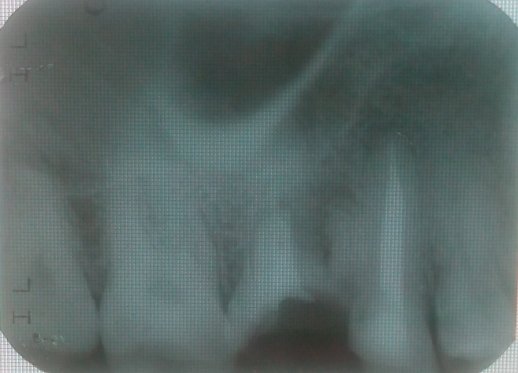

Здравствуйте. Беспокоит 7-ой зуб сверху слева (27). Зуб мертвый уже давно. Ноет, когда ему захочется. Иногда реагирует на температуру. Боль в обоих случаях терпимая, но неприятная. И сразу проходит. Мне его недавно залечили, прочищали каналы, положили туда хороший дорогой препарат, но это не помогло. Еще мне больно жевать что-то твердое. Боль ощущается то ли на этом зубе, то ли в промежутке между 7 и 6. В 1-ой клинике мне сказали, что есть гранулема и ее надо лечить с помощью микроскопа. Во 2-ой клинике мне сказали, что гранулемы нет. Прилагаю снимок.